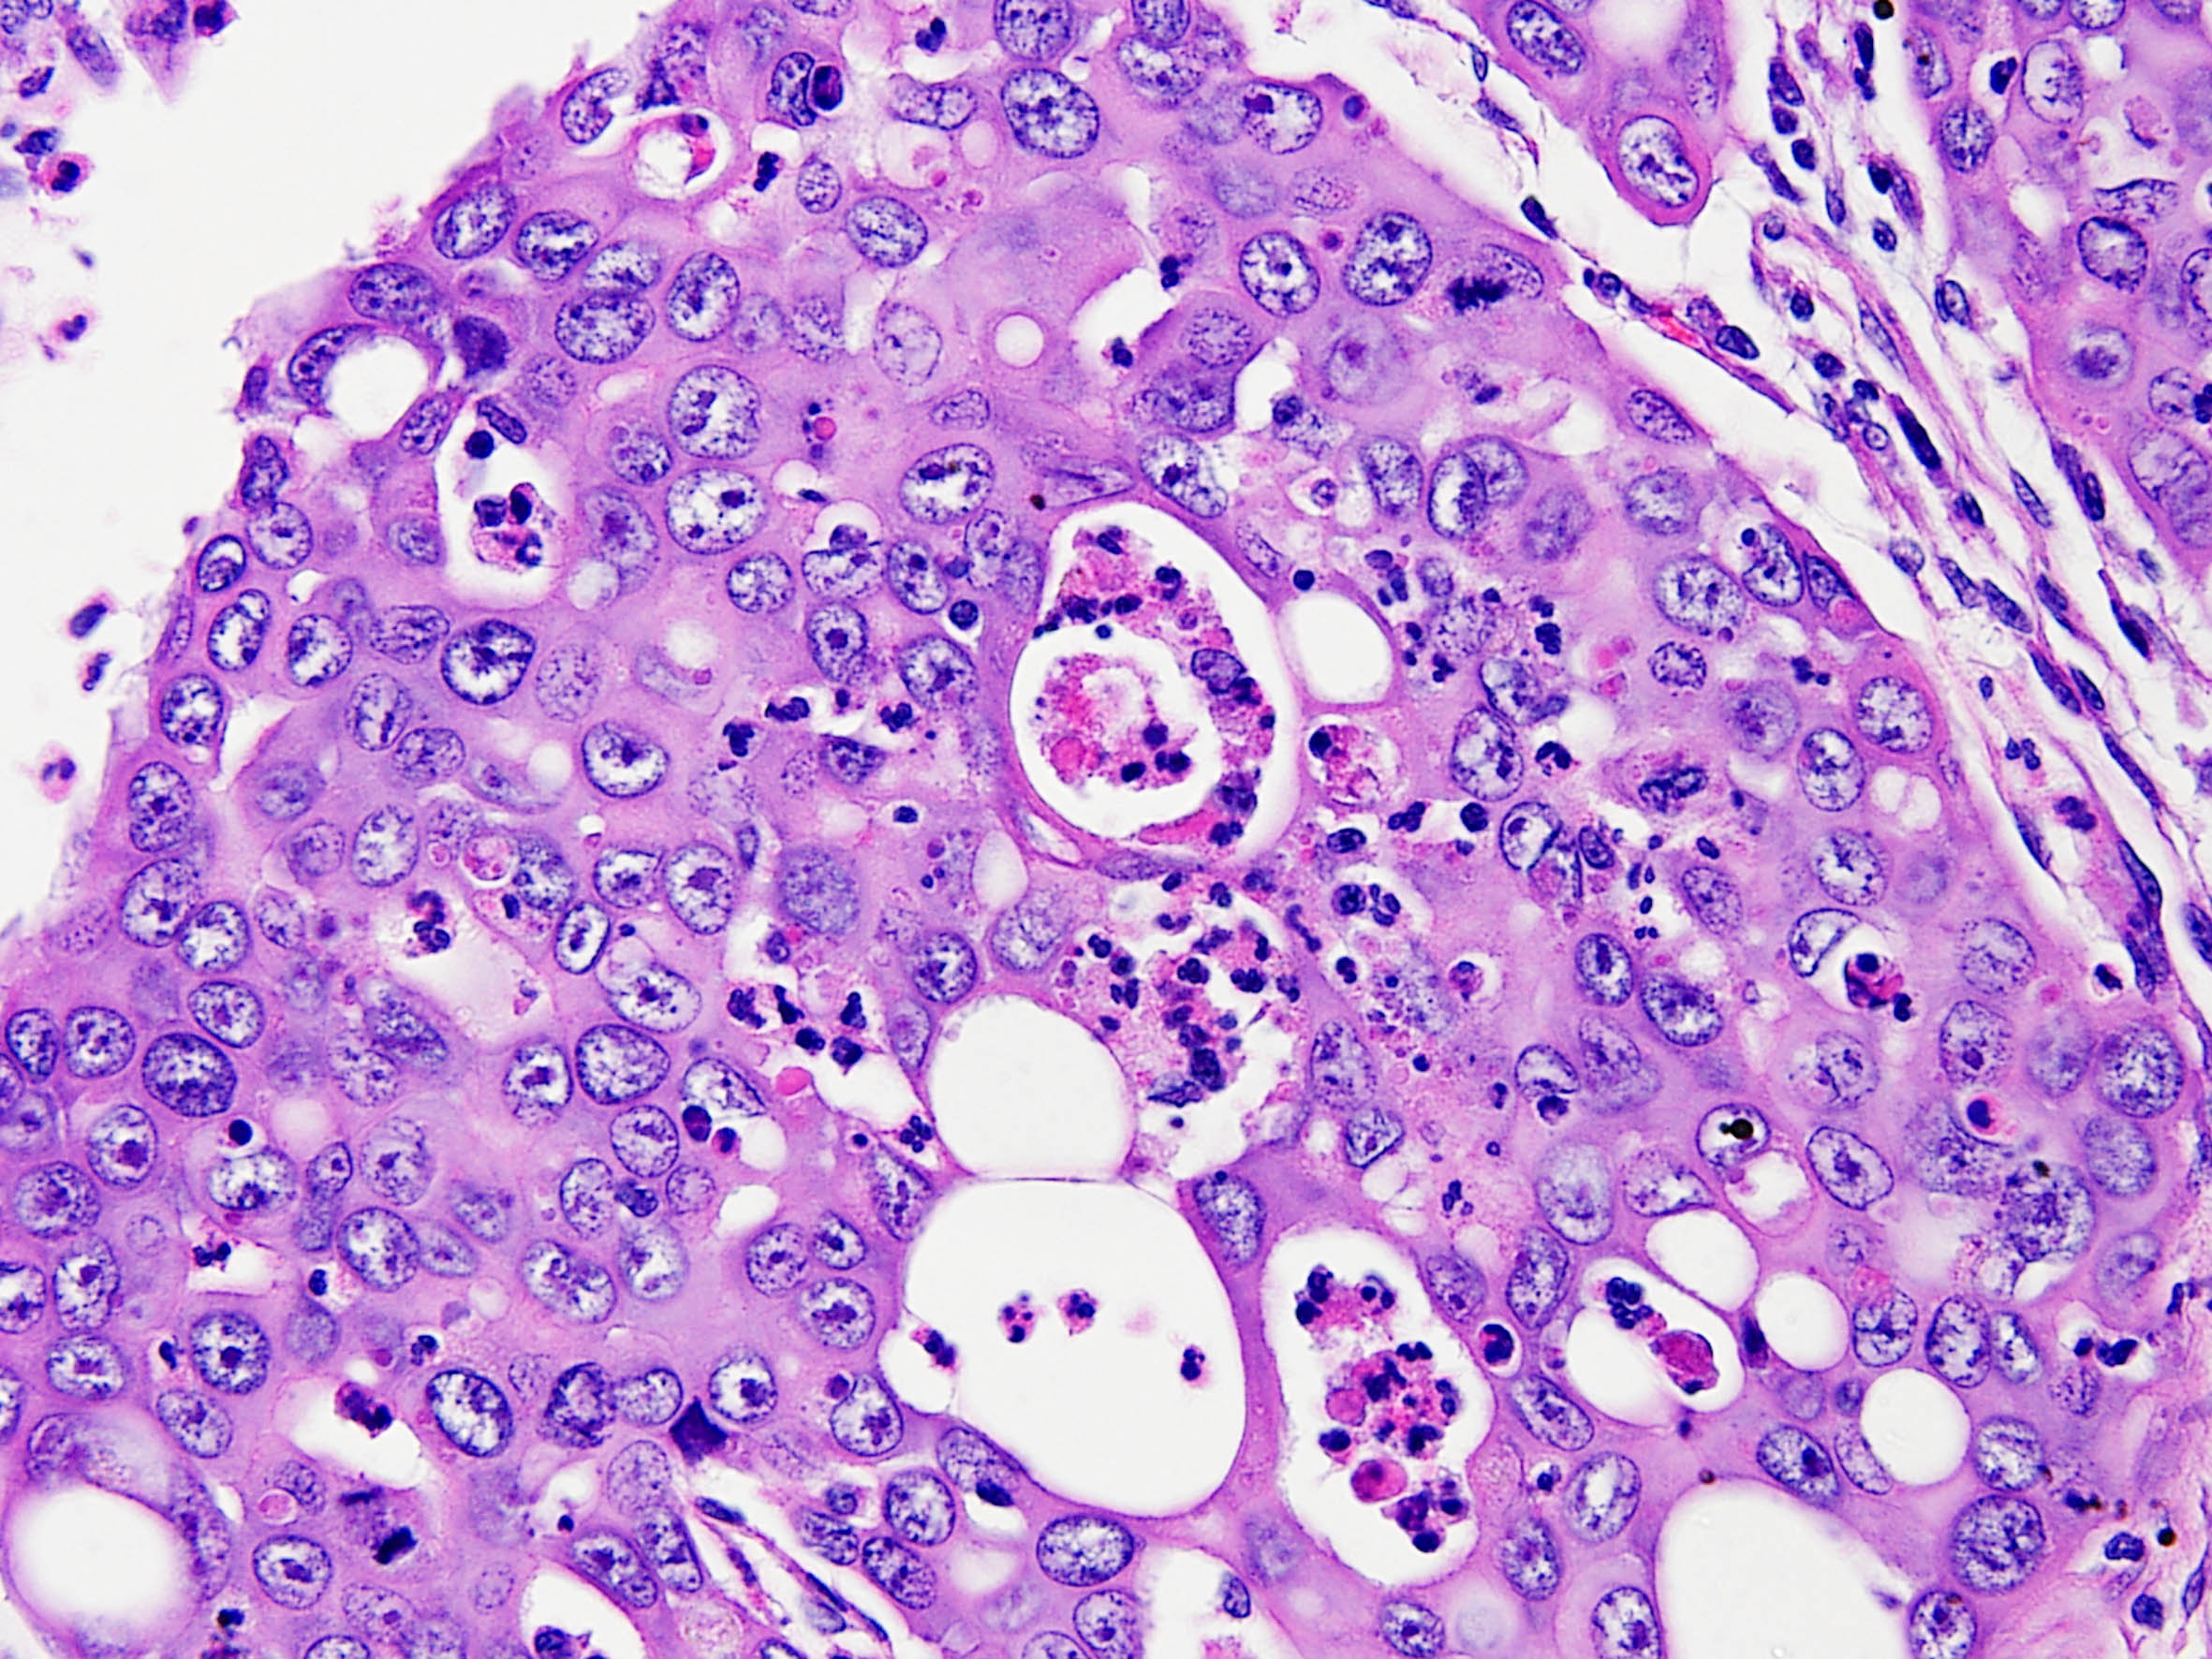

Consensus grade: Renal Medullary carcinoma

Case description (by case creator):

Renal medullary carcinoma